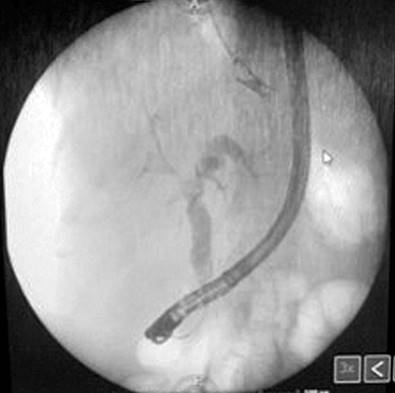

En su última visita, la paciente acude a la sala de emergencias con la sintomatología antes descrita, leucocitosis, aumento de las bilirrubinas, enzimas de colestasis (Tabla 1) e ictericia en la esclera y mucosas. Se valoró por el diagnóstico de colangitis, por lo que se realizó una colangiorresonancia, con la que se demostraron nuevos hallazgos a favor de múltiples lesiones quísticas intrahepáticas con captación anular del medio de contraste y dilatación de las vías biliares intrahepáticas, así como la extrahepática, hallazgos consistentes con enfermedad de Caroli. Se realizó una intervención con colangiopancreatografía retrógrada endoscópica (CPRE), en la que se efectuó una esfinterotomía previa canulación, y se observó la salida de coledocolitiasis y contenido seropurulento consistente con colangitis, y posteriormente se procedió a colocar una prótesis plástica de 10 Fr/9 cm (Figura 3).

Figura 3 CPRE en la que se observa contenido seropurulento consistente con colangitis. Fuente: expediente médico del paciente.